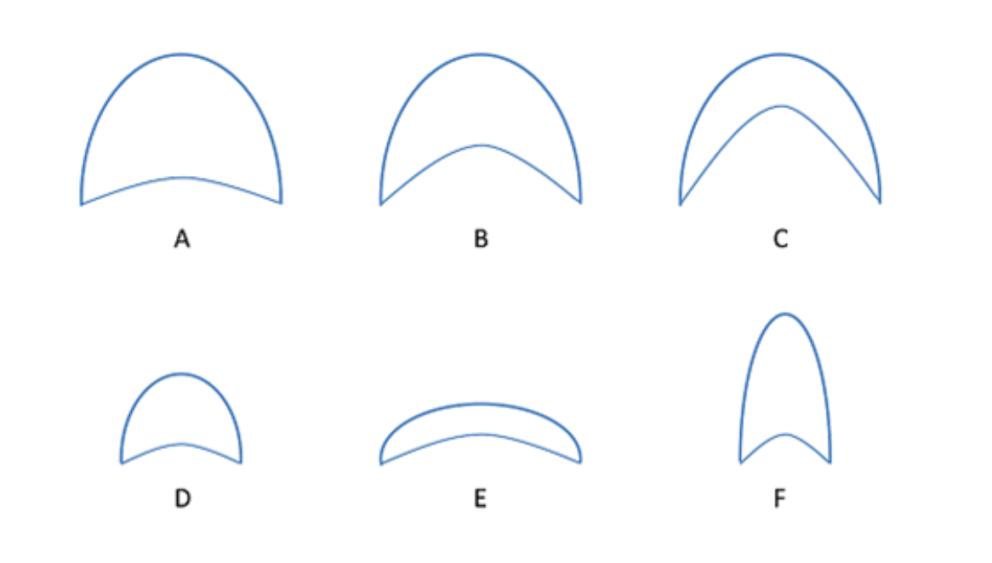

形态学分类法反映了不同类型气道狭窄的病理生理学基础,即根据呼气相气道横截面的形状变化对气道狭窄进行分类[7]。EDAC常表现为新月型,而TBM可表现为3种情况:圆周型、新月型和刀鞘型,见图 3。同时,形态学分类也可以为治疗方案的决策提供依据。

|

| A:正常气道吸气相横截面的形状;B:正常气道呼气相的横截面,此时气道膜壁向管腔内轻度凹陷;C:病理状态下,膜壁松弛,呼气相膜壁向管腔内过度凹陷,矢状面管径 < 吸气相50%;D:病变累及全部软骨,管腔呈圆周型缩小;E:病变累及软骨前壁,冠状面管径保持不变,管腔呈新月型狭窄;F:病变累及软骨两侧,管腔呈刀鞘样狭窄 图 3 中央气道狭窄的形态学分类 |

|

|